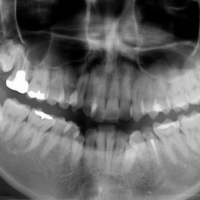

続きを読む歯科用CT

3次元の高画質画像が得られる歯科用CTを用いることで、見えなかった部分を容易に確認できます。これにより、さらに治療診断の精度を上げることが可能です。